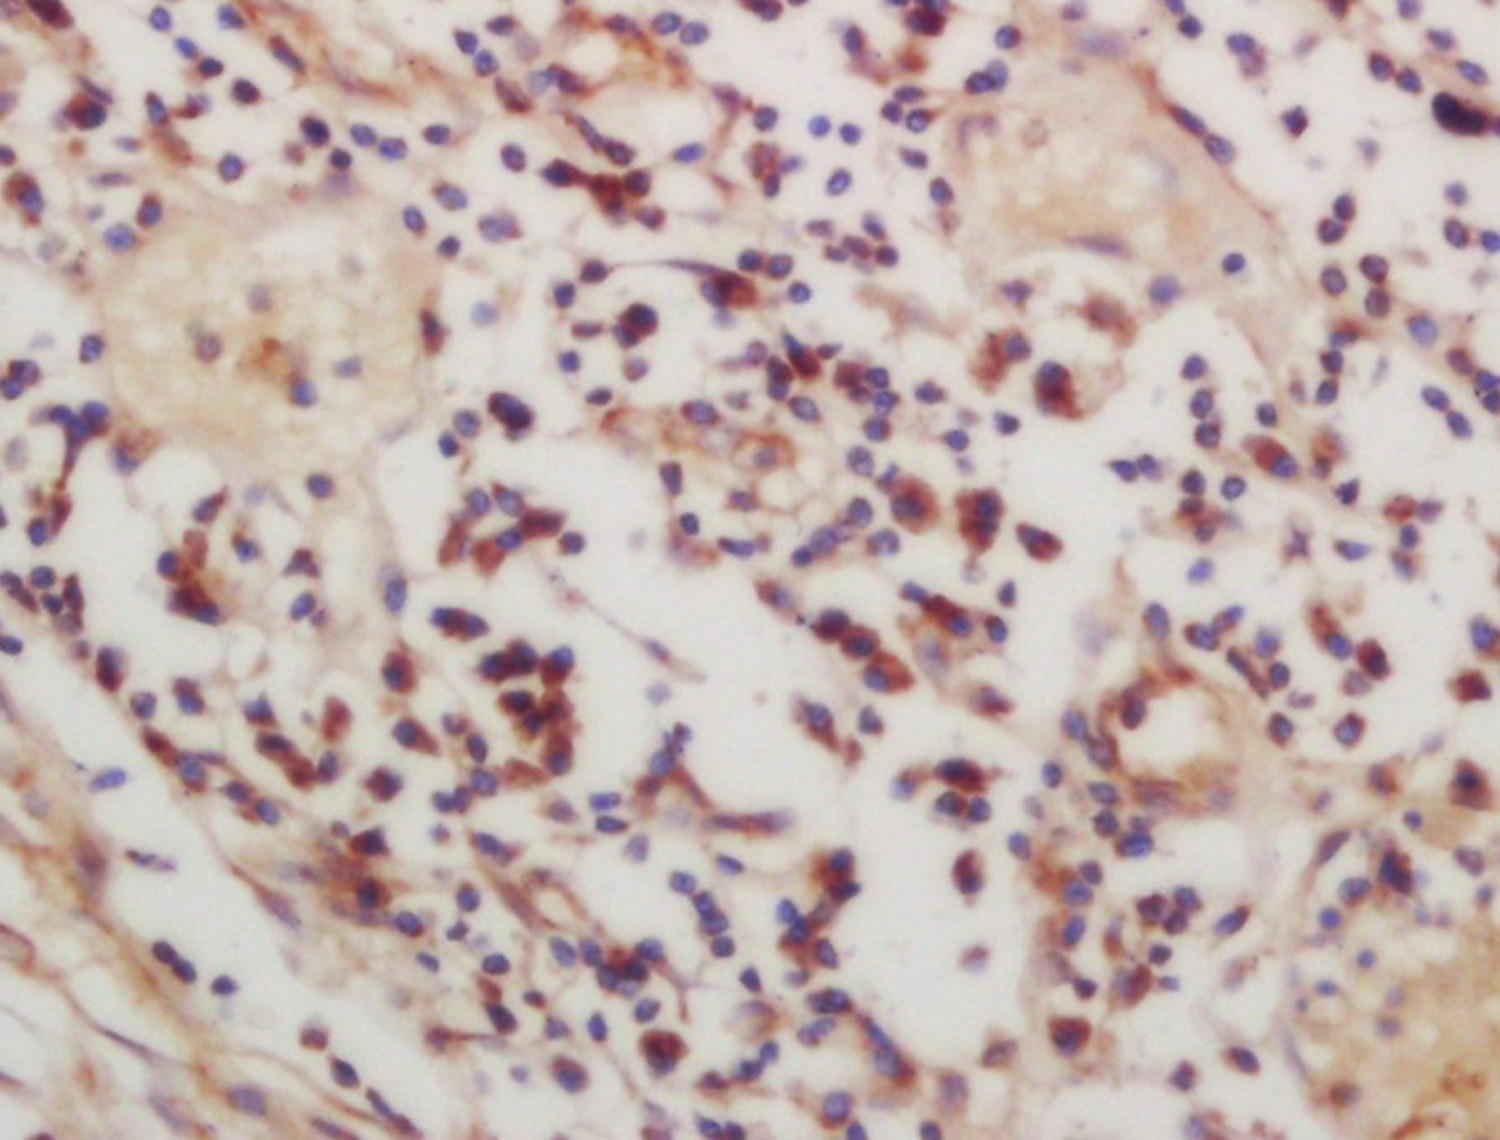

Tissue/cell: human lung carcinoma; 4% Paraformaldehyde-fixed and paraffin-embedded; Antigen retrieval: citrate buffer ( 0.01M, pH 6.0 ), Boiling bathing for 15min; Block endogenous peroxidase by 3% Hydrogen peroxide for 30min; Blocking buffer (normal goat serum,C-0005) at 37℃ for 20 min; Incubation: Anti-phospho-CSK(Ser364) Polyclonal Antibody, Unconjugated(bs-12942R) 1:200, overnight at 4°C, followed by conjugation to the secondary antibody(SP-0023) and DAB(C-0010) staining